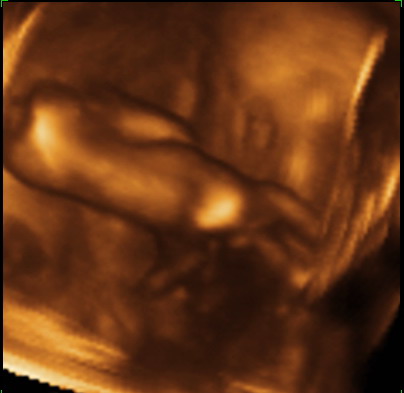

Nekunk remekul sikerult ez a koltozessel, utazassal es nyaralassal teli 3 het, bar mostanra nagyon elfaradtunk. Voltunk 3D-4D-s uh-n meg indulas elott, amit nagyon elveztunk. Kepzeljetek, nyitva volt a szeme, csuklott es ott sem volt hajlando megallni egy pillanatra sem. A kepek amiket kaptunk nem lettek tul jok, de igazabol mi most nem is a sztarfotok miatt mentunk, hanem szerettuk volna meg egyben latni, igy 20 hetesen. Viszont az egesz videon van, mar nem tudom hanyszor neztuk meg :) . A felvetelek vszleg csak nekunk szepek, tunderiek es edesek, lehet hogy ti majd csak egy kis ufonautat lattok benne, de hat ez van, ebben a korban kb ilyen kepekre lehet szamitani, bar van aki szerencsesebb. Mindenkepp akarok meg egyszer menni 3D-re, amikor mar nagyobb lesz, valamikor 30 het kornyeken. Nagyon nagy elmeny volt, ajanlom mindenkinek! A pocakom elkezdett szeduletes iramban noni, elkepeszto mennyit valtozik egy het alatt. Minden heten keszitunk rola kepet (ezt egyebkent mindenkinek ajanlom, ha meg nem csinalja) es nagyon muris egymas melle tenni oket... Szoval a pocak feszul, huzodik rendesen, de csak ritkan kemenyedek be. Diohejban ennyi, most mar gyakrabban fogok jonni, mert lassan vegzunk a pakolassal is.

Ez hatulrol van lekapva, mert elfordult. Szoval a tarkojat es a fekarjat lehet latni... (most mar nem olyan csonti :) )

Kép